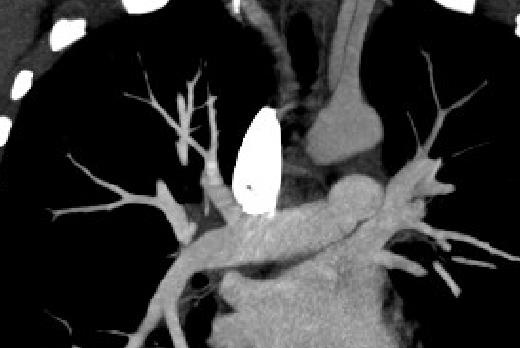

В первые сутки проведён системный тромболизис альтеплазой (рис. 1, 2; табл. 2), через 2-е суток выполнена кроссэктомия в связи с угрозой рецидива ТЭЛА.

Рис. 2. МСКТ-пульмонангиография пациентки В после тромболизиса.

Данные ЭхоКГ и МСКТ пациентки B до и после тромболизиса

Исследование | Исходные данные | Перед выпиской |

Эхокардиография | УЗ-картина острого лёгочного сердца с признаками перегрузки правых отделов сердца: дилатация полости ПЖ, парадоксальное движение МЖП, дилатация НПВ, умеренная лёгочная гипертензия (макс. СДЛА 45–50 мм рт. ст.). Аорта, створки аортального, митрального и трикуспидального клапанов не изменены. Размеры левых отделов сердца, толщина стенок в норме. Глобальная сократительная способность миокарда ЛЖ сохранена, зон нарушения локальной сократимости не выявлено | Гипертрофии миокарда нет. По сравнению с предыдущим исследованием — положительная динамика, уменьшение признаков перегрузки правых отделов сердца, несколько уменьшилась в размерах полость ПЖ, сохраняется парадоксальное движение МЖП, отмечено незначительное уменьшение диаметра НПВ, есть реакция на дыхание, лёгочная гипертензия снизилась до незначительной (макс. СДЛА 35–40 мм рт. ст.) |

Компьютерная томография грудной клетки | Мультифазная МСКТ органов грудной полости с внутривенным болюсным контрастированием: массивная тромбоэмболия в бассейне обеих лёгочных артерий без явных патологических изменений со стороны лёгочной ткани | Значительное уменьшение количества и выраженности дефектов наполнения артериального русла малого круга кровообращения; сохраняются значимые тромбозы обеих нижнедолевых артерий, больше слева. На этом фоне отмечается формирование воспалительных изменений в нижней доле левого лёгкого |

Примечание. ПЖ — правый желудочек; МЖП — межжелудочковая перегородка; НПВ — нижняя полая вена; СДЛА — среднее давление в лёгочной артерии.